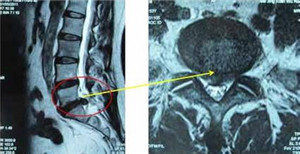

腰椎间盘突出引起腰疼

腰椎间盘突出会表现腰痛,部分病情严重者臀部、腿部还会出现放射性疼痛。刺痛明显。>>>【点击咨询】疼起来坐立不安,怎么缓解?